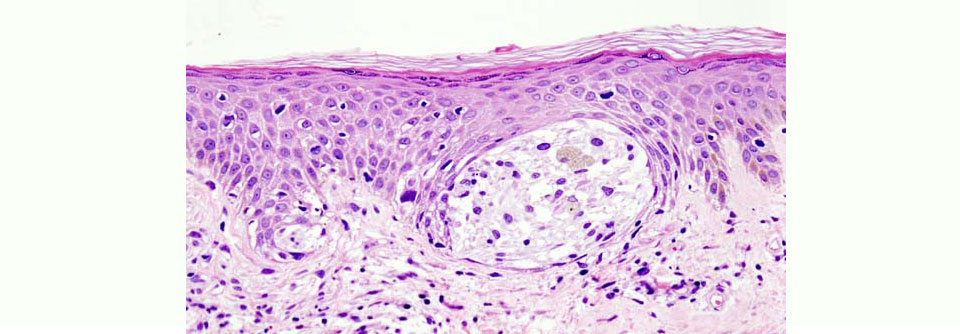

40 Melanome (83 %) wurden als kutan definiert und 8 (17 %) als okulär, mukosal oder ohne bekannten Ursprung (melanoma of unknown primary, MUP). Von den kutanen Tumoren fielen 30 (75 %) auf die Haut an Händen, Füßen oder Nägeln (Akren), wobei meist die Ferse oder die Fußsohle betroffen war. 10 der 30 Läsionen (33 %) wurden ­his­tologisch als akral-lentiginös klassifiziert, 12 (40 %) als in situ, 1 (3 %) als Spindelzellmelanom und in 7 Fällen (23 %) gab es keine Spezifikation. Von den zehn nicht-akralen kutanen Tumoren erwiesen sich 3 (30 %) als superfiziell spreitend (SSM) und 3 (30 %) als desmoplastisch.